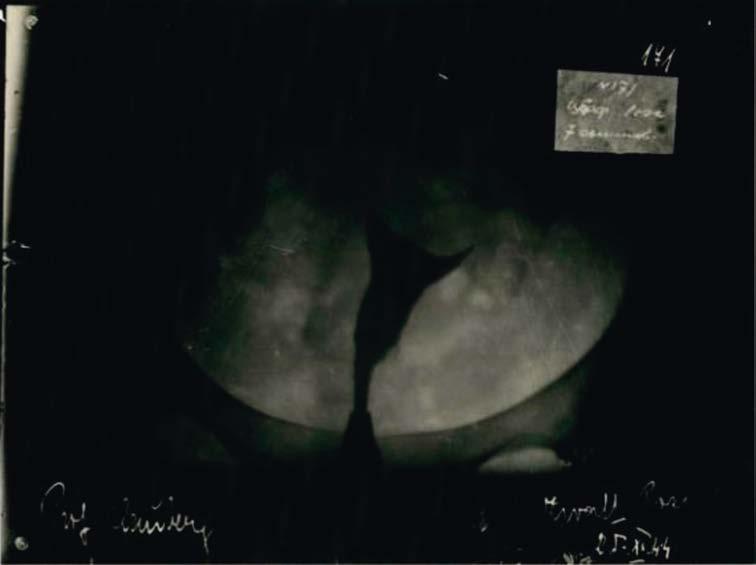

Photo 1.  |  A hysterosalpingogram of prisoner Rosetta Zwaaf with information referenced in the main body of the text marked: 1—the name of prof. Clauberg; 2—the three-digit identification code. 3—the name of the prisoner; 4—the date. Source: Archives of the Main Commission of Investigation of Nazi Crimes in Poland (Archiwum Głównej Komisji Badania Zbrodni Hitlerowskich w Polsce), ref. No. DDM 15428, now in the possession of the Polish Institute of National Remembrance

According to Głowacki, the X-rays were the world’s only remaining original piece of evidence that documented Clauberg’s criminal experiments. All of the ra diological images are the same size: 18 centimeters high and 25 centimeters wide. Each image shows a uterus. To the lower left of the images appears the name “Prof. Clauberg” and to the lower right, a woman’s name appears with the date “1944” just below it. In the upper right corner, a three-digit code is given. In total, there are seven different women’s names and seven different codes. The codes and the numbers clearly correspond to each other. On nine of the 26 images, the com pany name “Agfa” can be seen along the left side of the image. According to the his torical records, no less than 2 and no more than 7 such images were taken of each person between February 28 and November 26, 1944. The last of these images were produced on November 25 and 26, a Saturday and Sunday. These were presumably Clauberg’s last X-rays from Auschwitz.4

The radiological images were produced as a part of a hysterosalpingographic procedure, during which the Fallopian tubes are examined.5 Towards the end of the 1920s, this gynecological procedure had become established as a reliable diag nostic method for ascertaining tubular blockage. Between 1928 and 1929, during his training as a medical consultant at the University Hospital of Kiel (Germany), Clauberg had become familiar with this technique. Clauberg’s experiments, par ticularly those on hormonal therapies for tubal occlusion, were published in nu merous scientific journals and made him well-known both inside and outside of Germany.

Explained briefly, Clauberg’s plan was to employ a modified version of the tra ditional hysterosalpingography. The first step was to use X-rays to document how open the women’s Fallopian tubes had been before the procedure. Then, in the sec ond step, instead of a pure contrast medium, a solution which contained forma lin was injected. The purpose of this admixture was to first cause tubal adhesions and then make them visible on the radiological image. In the third step, Clauberg tested the extent to which the tubes had become blocked. Throughout the entire trial, multiple examinations were conducted to monitor the process.

In the document, seven women were named and assigned a case-num ber: Hedwig Cohen (No. 205), Fanny Ettinger (No. 190), Sara Noord12 (No. 219), Barbara Smolensky (No. 138), Selma Spijer (No. 173), Jetta Vosch (No. 223) and Rosetta Zwaaf (No. 171). In response to initial inquiries made in the Warsaw ar chives, on May 29, 1967, the Director of the Auschwitz Museum in Oświęcim in dicated that the archival files only contain information about Fanny Ettinger. According to their records, Fanny had apparently been born on February 18, 1895 in Kyiv and on July 20, 1943 she arrived in Auschwitz in a deportation transport from Drancy. This piece of information was ascertained from surviving transporta tion lists. Neither Ettinger’s camp number nor her fate are known. What is known, however, is that several women from that transport were sent to Block 10. In re

As for the four remaining names on the radiological images, in 1974 the Auschwitz Museum had no information on them. However, based on other sources, it is possible to determine with some degree of certainty that the four per sons were Dutch women who survived Auschwitz. Sara Noord and Rosetta Zwaaf ar rived in Auschwitz on August 26, 1943 in a transport from Westerbork. Sara Noord (born December 12, 1915 in Amsterdam) was tattooed with the camp number 56003, and Rosetta Zwaaf (born February 19, 1904 in Leiden) was tattooed with the num ber 56016. Selma Spijer and Jetta Vos arrived in Auschwitz on September 23, 1943. Like Sara Noord, they had also come as part of a transport from Westerbork. Selma Spijer (born February 19, 1921 in Utrecht) was issued the camp number 63235, while Jetta Vos (born March 27, 1908 in Amsterdam) received number 63252. All four Dutch women testified after their liberation that they had been given a sterilization injection in Block 10 or in Block 1. Selma Spijer and Jetta Vos were never able to have children. Rosetta Zwaaf, however, bore one son and Sara Noord had two sons.